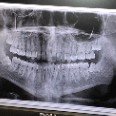

早上 ,帶家瑋去朋友的牙科,計劃是照X光,再約拔智齒時間。

他下面的智齒已經橫著長出來,

上面兩顆一拔就出來,下面兩顆挖了好一陣子.

傳教士申請書,體檢牙齒部分全部完成!